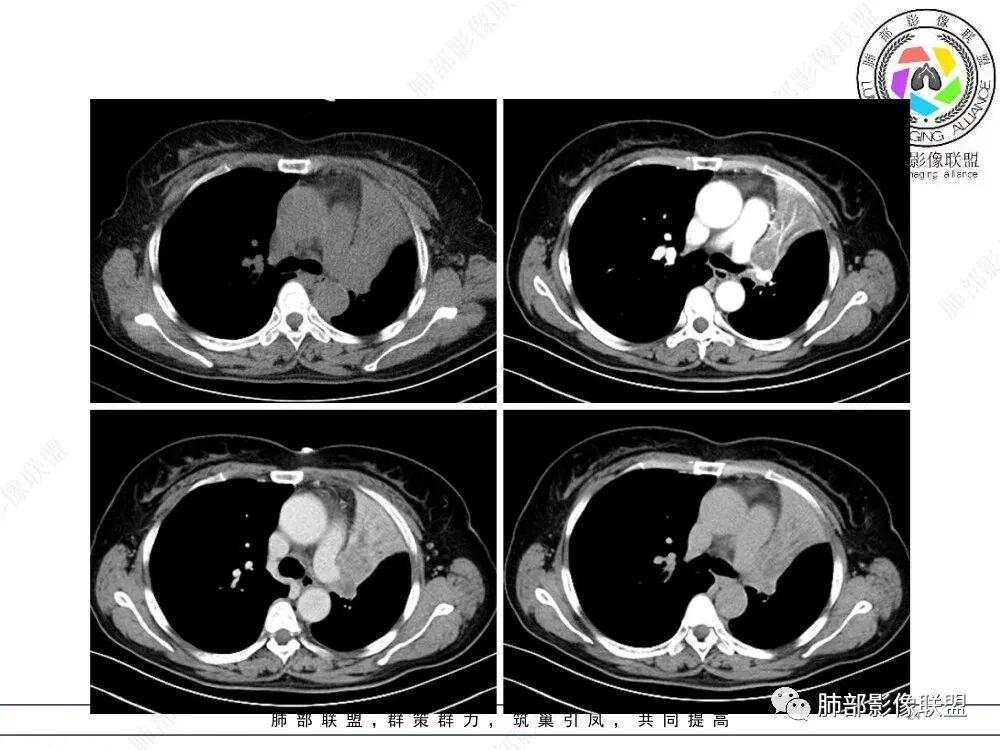

1、简要病史:老年女性,以受凉后咳嗽伴胸闷就诊,无咳痰、发热及其他不适,病程4月;既往体健。实验室检查中性粒细胞稍高,PCT稍高,CEA、细胞角蛋白19片段、鳞状细胞癌抗原正常。

2、影像表现:正常肺背景,左肺上叶支气管腔内占位,上叶支气管截断,远端肺组织不张,强化差异衬托出肺门区结节影或块状影。增强扫描腔内占位轻中度不均匀强化,可见坏死,远端粘液栓,局部肺动脉受压、侵犯,纵膈淋巴结无明显肿大,无胸腔积液。

④小细胞肺癌属于高度恶性神经内分泌肿瘤,好发于吸烟男性,多数小细胞癌影像表现较典型,表现为肺门旁或外周边缘膨隆、边界清楚的软组织结节或肿块,由于肿瘤组织坏死不彻底,常表现为“沼泽样”坏死区,较早出现肺门和纵膈淋巴结转移,有“娘小崽大”的特点。纵隔淋巴结融合,可形成“冰冻纵膈”。小细胞癌侵袭力强,容易包埋血管形成“血管包埋征”,肿瘤沿支气管浸润时可见病灶呈鸭蹼和腊肠样凸起,相较于鳞癌而言,小细胞癌导致的阻塞性肺炎常常较轻,较少合并肺不张,少见合并胸水。

就本例而言,患者为女性,无肺气肿背景,未提及吸烟史,影像上强化程度偏轻,未见湖泊样坏死,尽管中央型肺癌中以鳞癌最多见,且造成完全阻塞及肺不张,但在女性患者诊断鳞癌仍需谨慎。支气管腔内结节,强化程度轻,涎腺肿瘤需要考虑,不典型类癌也不能除外。女性患者,未提及吸烟史,尽管未见纵膈淋巴结明显肿大,但支气管明显相关,小细胞肺癌亦应当重点排除。